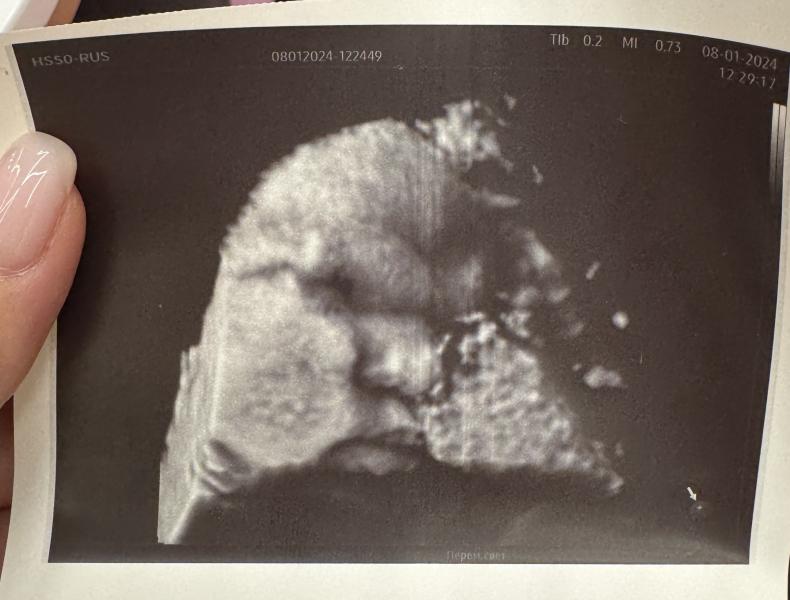

37 недель 4 дня

Делали плановое УЗИ

Шейку еле еле 15 мм намерили , внутренний зев открыт до 6 мм

На кресле не стали смотреть, так как завтра еду в роддом , на плановый осмотр, но врач сказал приблизительно 1-2 пальца

Поставили маловодие , малышке бедной совсем там тесно(( Сказали могу родить в ближайшее 2-3 дня, надеюсь завтра меня оставят в Роддоме 🙄

Наша сладкая булочка🥰

Вся в папу и носик, и губки, надеюсь хотя бы характер будет в меня😂

Весим 1,5 кг, лежим головкой вниз))порядочная мадам)))